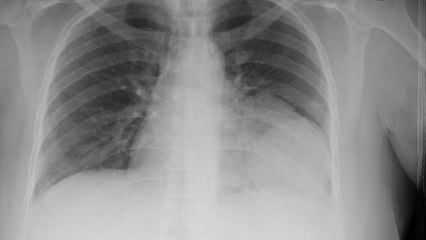

Child born with heart in the right hand side